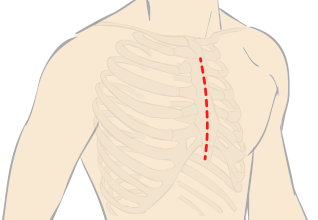

”弁の損傷が思ったより激しいため、当初予定していた、小切開ではなく、正中開胸で、弁形成の術式で手術をすることになった”と説明を受けた。

”体が扁平なので小切開手術ではなく、正中切開になる”と言われた。

“ダビンチ”キーホール手術は、手術支援ロボット“ダビンチ(da Vinci Surgical System)”を用いたロボット手術です。開胸することなく、骨を切らず、数カ所のキーホールからすべての操作が遂行できるので、術中の出血が少なく、術後の痛みも軽く、また大きな傷が残らないため美容的にも優れています。従来のように人工心肺などを使用して遂行していた手術が“ダビンチ(da Vinci Surgical System)”の出現により劇的に変化し、術後経過や術中の体への負担が軽減できるようになりました。“ダビンチ(da Vinci Surgical System)”のような内視鏡手術の進歩は心臓だけでなく、すべての領域で目覚ましい発展を遂げています。現在では珍しいものでは無く標準の手術方法として認められる傾向にあり、新たなアプローチとして広い分野で採用されています。

手術支援ロボット“ダビンチ”を使用したロボット手術は、骨を切らずに小さな傷口のみでオペを行い、出血量・痛みの減少を実現します。早期の社会復帰が可能な手術です。

〈 外科的アプローチ 〉

従来の治療アプローチと

ダビンチ“キーホール手術”の違い

胸を大きく切り開く心臓疾患手術方法以外の手術方法はありますか?

手術支援ロボットのダビンチによる手術や小切開手術が可能な場合がございます。ダビンチの手術は小さな3つの穴から手術を行うため従来の方法より痛みや傷の感染、出血量が軽減。